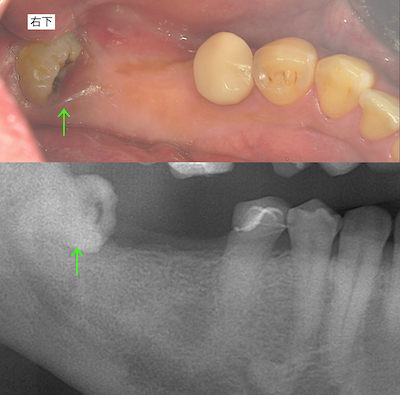

右下です。

初診時と術後のレントゲンです。